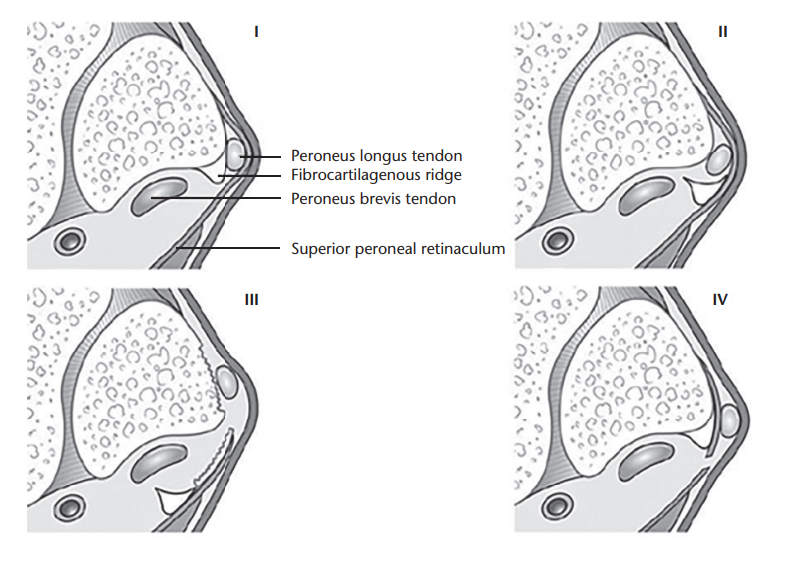

动态超声允许实时评估脱位时腓骨肌腱的异常运动,特别是配合踝关节内翻、跖屈位背伸、外翻活动,有助于发现 CT 和 MRI 假阴性静态成像结果。

患肢踝关节处于中立位时获得的轴位超声图显示腓骨远端 (F) 后方的腓骨长肌 (L) 和腓骨短肌 (B) 肌腱处于正常关系。图源:DOI:10.2214/ajr.183.4.1830985